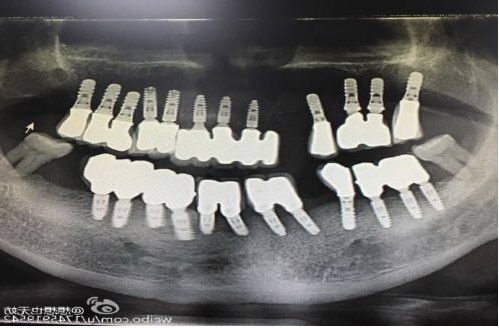

赖仁发教授经典案例:没有条件种,创造条件种

赖仁发教授经典案例:“沙漠”上创造出绿洲

种植体有长,有短,有细,有粗

因为种植牙,生活更美好

“愿每个缺牙老人都能吃、能喝、能咬、能唱!”这是赖仁发教授一直在力行的独到理念。种植牙的品质和效果是考核种植牙医生的关键要素,赖仁发教授这样说也是这样做的,工作中,他不仅身体力行践行严格的医疗管理理念,而且还严格要求整个医疗团队,暨南大学附属一院穗华口腔医院种出来的每颗牙都经得起时间的考验,才能获得越来越多的市民信赖。